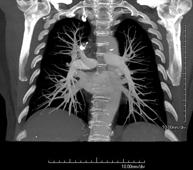

- Angio-TC Arterias pulmonares (Estudio TEP, Tromboembolismo Pulmonar)

Prueba diagnóstica que consiste en el estudio de las arterias pulmonares mediante el empleo de un equipo de TC (Tomografía Computarizada) obteniendo imágenes bi y tridimensionales. En este estudio es imprescindible el uso de contraste yodado, el cual permitirá una mejor definición anatómica. Esta prueba está principalmente indicada en los casos de sospecha de tromboembolismo pulmonar (TEP) para descartar o confirmar la presencia de coágulos sanguíneos en el interior de las arterias.